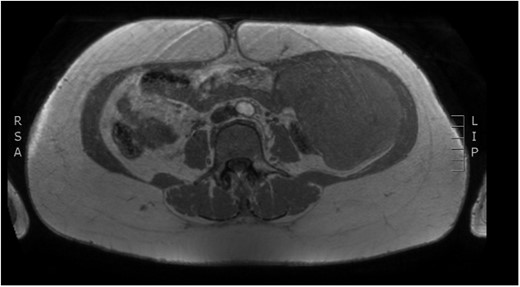

Physical examination revealed a painless, mobile parietal mass on the left anterior abdominal wall, more prominent during cough, of ~13 cm in diameter, with smooth contour and without skin involvement. Laboratory examination including cancer marks showed results within normal limits; hydatid serology (IgG antibodies) was also negative. As ultrasonography results were inconclusive, further imaging with magnetic resonance imaging (MRI) revealed a sizable cystic mass measuring 10 × 13.4 × 11.7 cm, located in the left anterior abdominal quadrant, in the paraumbilical region, between the left internal oblique and the transversus oblique muscle, with projection to the inferior surface of the rectus abdominis. The mass was characterized as a thin-walled cystic lesion, with delayed uptake of intravenous contrast of the wall. High signal intensity was observed on T1-weighted images and low signal intensity on T2-weighted images, with high probability of neoplasia or bleeding (Figs 1–3). No other abdominal or pulmonary lesions were present.

Preoperative MRI. T2 weighted image. Low sign density of the lesion.

The diagnosis of hydatid disease relies on clinical findings, imaging techniques and serology. MRI findings, in particular, that are consistent with hydatid cyst include low-signal-intensity rim on T2-weighted images, which represents the collagen-rich pericyst, whereas cyst material presents hypointense, relative on T1- weighted images and hyperintense on T2- weighted images. Abscess, persistent hematoma, synovial cyst and neoplasia, such as sarcoma and liposarcoma, should be included in the differential diagnosis [4, 5]. Our patient lived in an endemic rural area; however, no previous history of hydatid disease was present, while serology and MRI findings were inconclusive, therefore preoperative diagnosis, could not be precise.